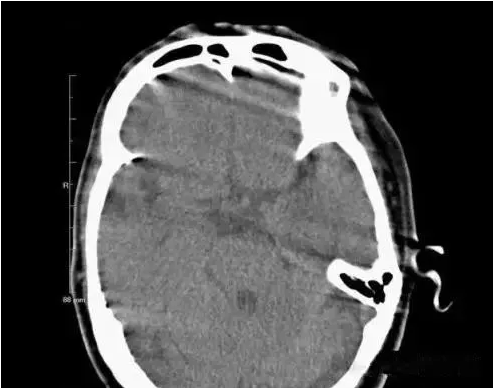

(運動偽影)

在掃描過程中,如果病人體位發生變化,可造成圖像數據排列紊亂。重建圖像結構模糊,無法分辨。運動偽影又分為自主運動偽影和生理性運動偽影。